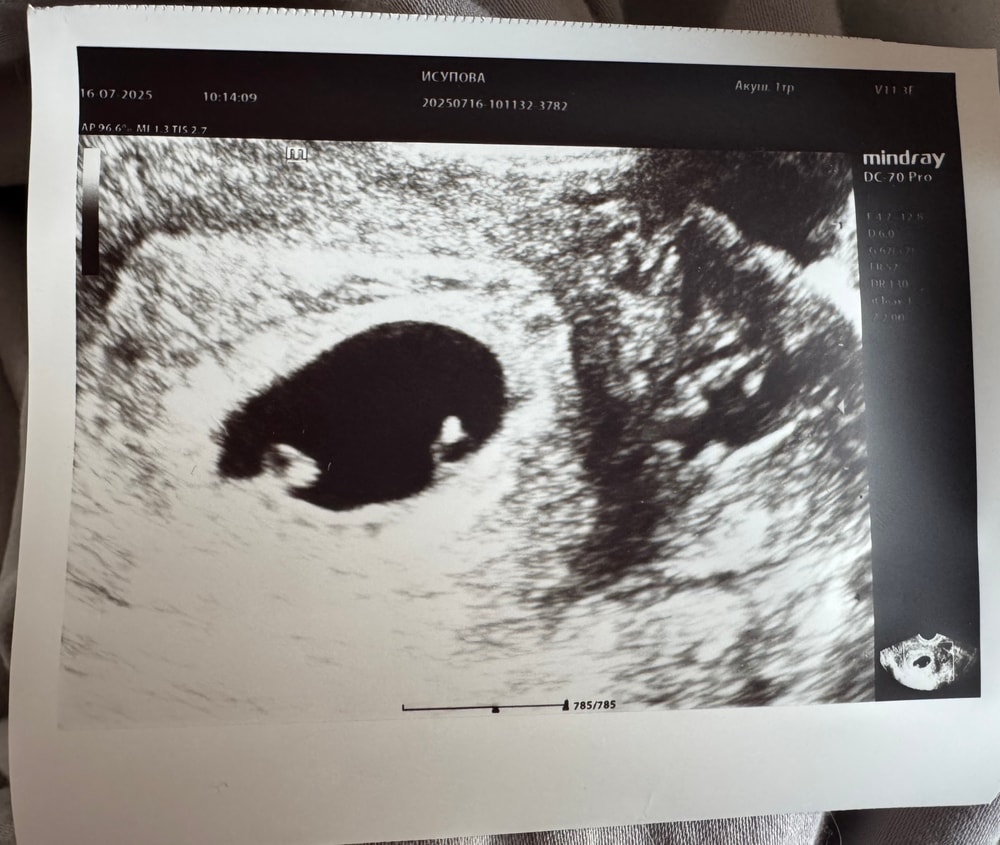

Девочки, подскажите, почему-то не могу опубликовать вопрос, может тут кто ответит У меня по последней менструации 6 недель 1 день, сегодня весь день тёмно коричневые выделения, к гинекологу так и не попала, но сходила на узи, сказали что всё хорошо, но срок не соответствует, всего 3 недели. Сказали ещё прийти через 8 неделю, так вот, когда вышла начала рассматривать снимок и вижу там 2 одинаковых "пятнышка", может ли это двойня? Или это что-то другое? Изображение